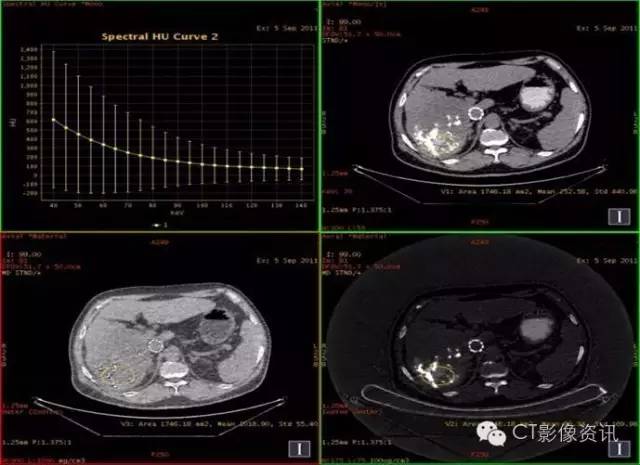

病史资料 男性,56岁,肝癌栓塞术后复查。

扫描参数 模式:GSI-22 375mA@0.7sec/rot@DC40mm@SFOV Body Large 螺距:0.984:1 平扫+增强扫描

结论:此例平扫、增强多期碘基物质定量无显著差异。栓塞治疗效果较好。

临床优势 肝癌栓塞后,因碘油和术后炎性反应的影响,短期内难以评估手术效果。通过能谱成像GSI分析,比较增强后碘含量与平扫时碘含量(有时可用水含量)的变化及变化趋势,来判断肝癌病灶是否还有强化,评估栓塞治疗的疗效和预后,并可指导临床进一步治疗。